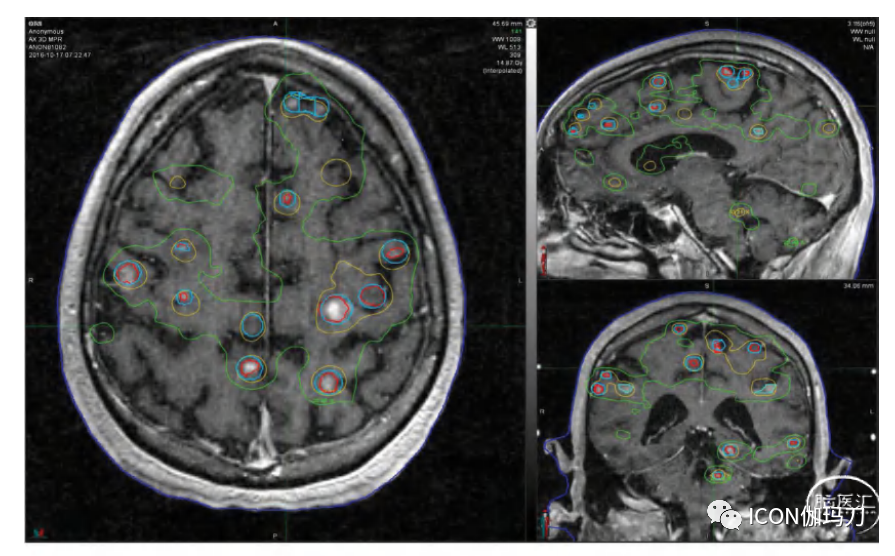

早期建模研究表明,SRS治疗25个脑转移瘤,保持每个转移瘤的最大点剂量<40Gy,会导致全脑剂量达到脑体积的50% (D50) <5Gy 。此外,模型显示,与肿瘤的实际数目相比,肿瘤总体积更能预测平均全脑剂量和全脑累积剂量。然而,平均全脑剂量与肿瘤总体积的确切关系可能并不总是可预测的,因为在肿瘤数目和/或肿瘤体积较大的情况下,处方边际剂量可能会减少,以试图降低放射副作用的风险。图32.1显示,当对多个治疗疗程的剂量进行汇总时,12Gy等剂量线可在较大比例的大脑区域重叠,潜在地增加副反应发生的可能性;在本例中,处方边缘剂量在随后的SRS疗程中减少。

图32.1我们纽约大学(NYU)研究中治疗体积最大的患者的T1多平面重建(MPR) MRI和全脑剂量体积直方图(DVH)。该患者共接受了5次治疗,共治疗112个肿瘤。在将所有疗程的剂量与10.2Gy的累积平均全脑剂量相加后,12Gy等剂量线(绿色)有显著重叠。这个图像用于计划第五个疗程。患者最初出现20个肿瘤,并接受了17Gy边缘剂量的治疗。在随后的治疗中,边缘剂量降低到16Gy、15Gy、14Gy和11Gy。较粗的蓝线显示早期不同程度的肿瘤反应的边缘剂量。红线是医生绘制的肿瘤轮廓线,黄线是累积20 Gy等剂量线。